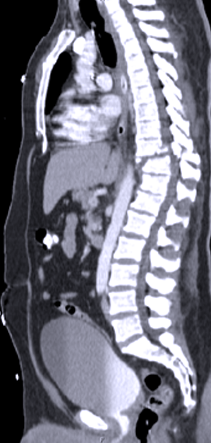

Spinal Trauma and Fractures

Spinal injuries can be serious life threatening problems that cause paralysis requiring complex surgical repair and others are lesser injuries that my only result in transient pain that are treated with a brace or collar while they heal. Fractures can occur in various regions of the spine and must be evaluated by a spine surgeon with experience in these injuries.

Some of those complex problems can also now be treated with minimally invasive techniques developed recently that avoid major surgical procedures. Dr Johnson’s experience in all types of spinal fractures dates back the mid 1980’s at UCLA then Cedars Sinai where he was also Director of the Spine Trauma Program. Subsequently he has trained many surgeons throughout the country who now treat spinal fractures on a regular basis.